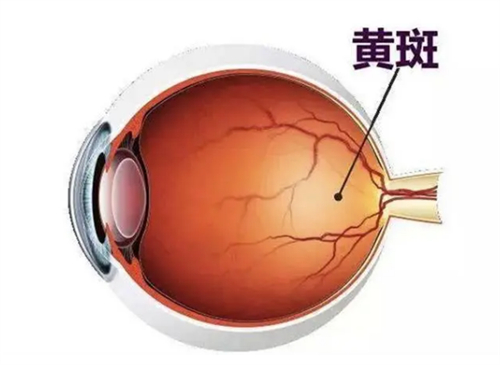

设备靠前,术前检查超全(OCT、角膜地形图等)。